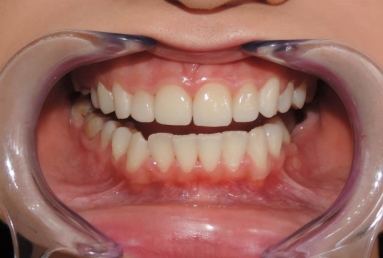

Very small lateral incisors covered with full ceramic crowns and ceramic veneers on central incisors. The prosthetic space was correctly split between the four incisors, in order to reduce the disproportion between the large centrals and the very small laterals. The preparation of the teeth was minimally invasive, all four incisors remained vital.